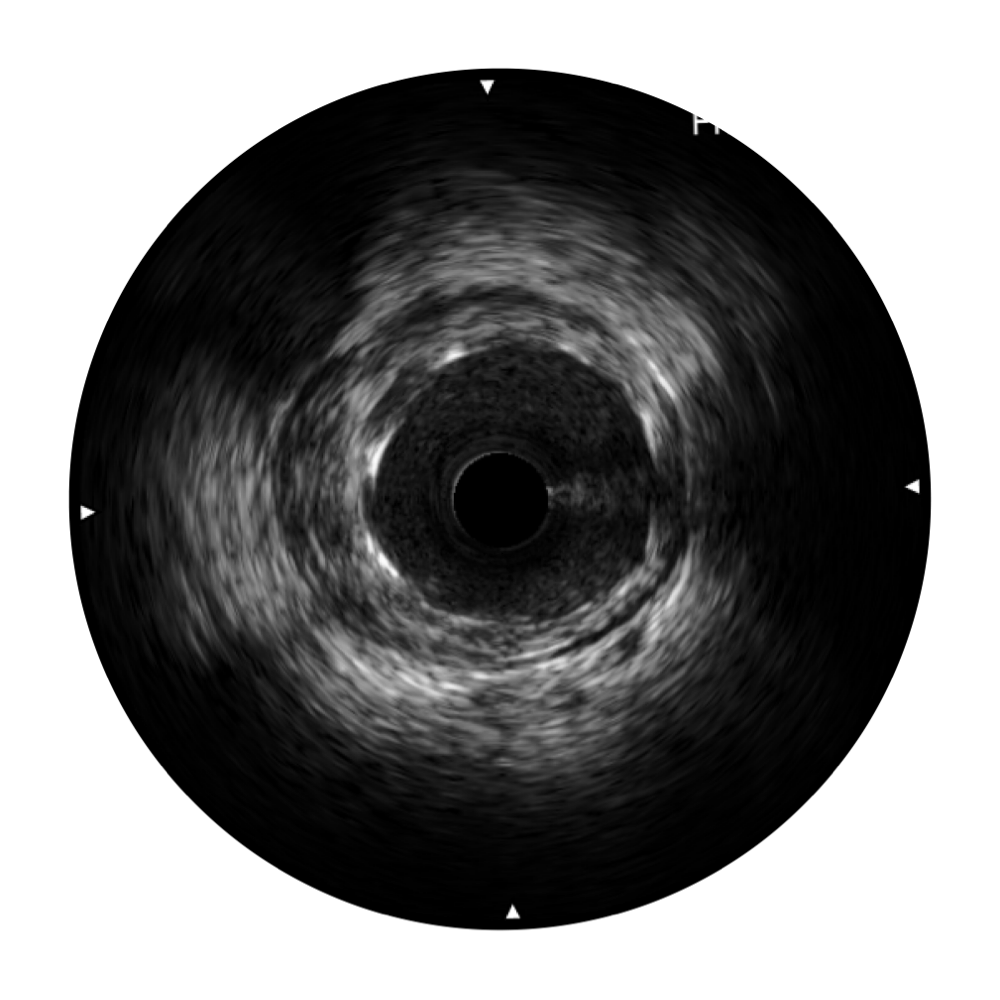

百老汇电子游戏官网宽频IVUS图像

传统IVUS图像

对比传统IVUS导管成像,百老汇电子游戏官网宽频IVUS图像的近场支架梁显影更细腻,远场中膜外血管仍清晰可辨,兼顾远中近,兼顾分辨力与穿透深度